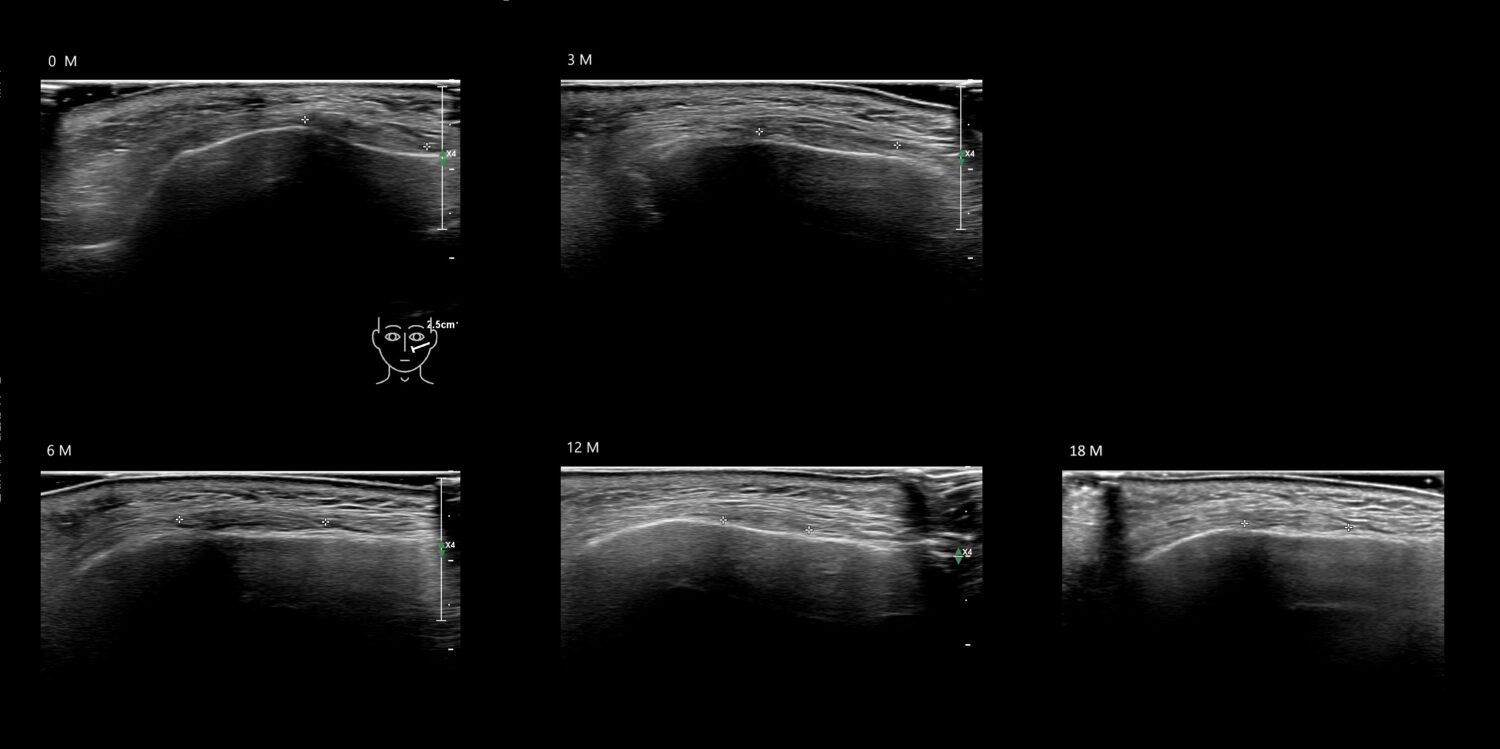

Fillers

Draw in the image on the right where the fillers are located. To check if your answer is correct, please click on the secondary image.